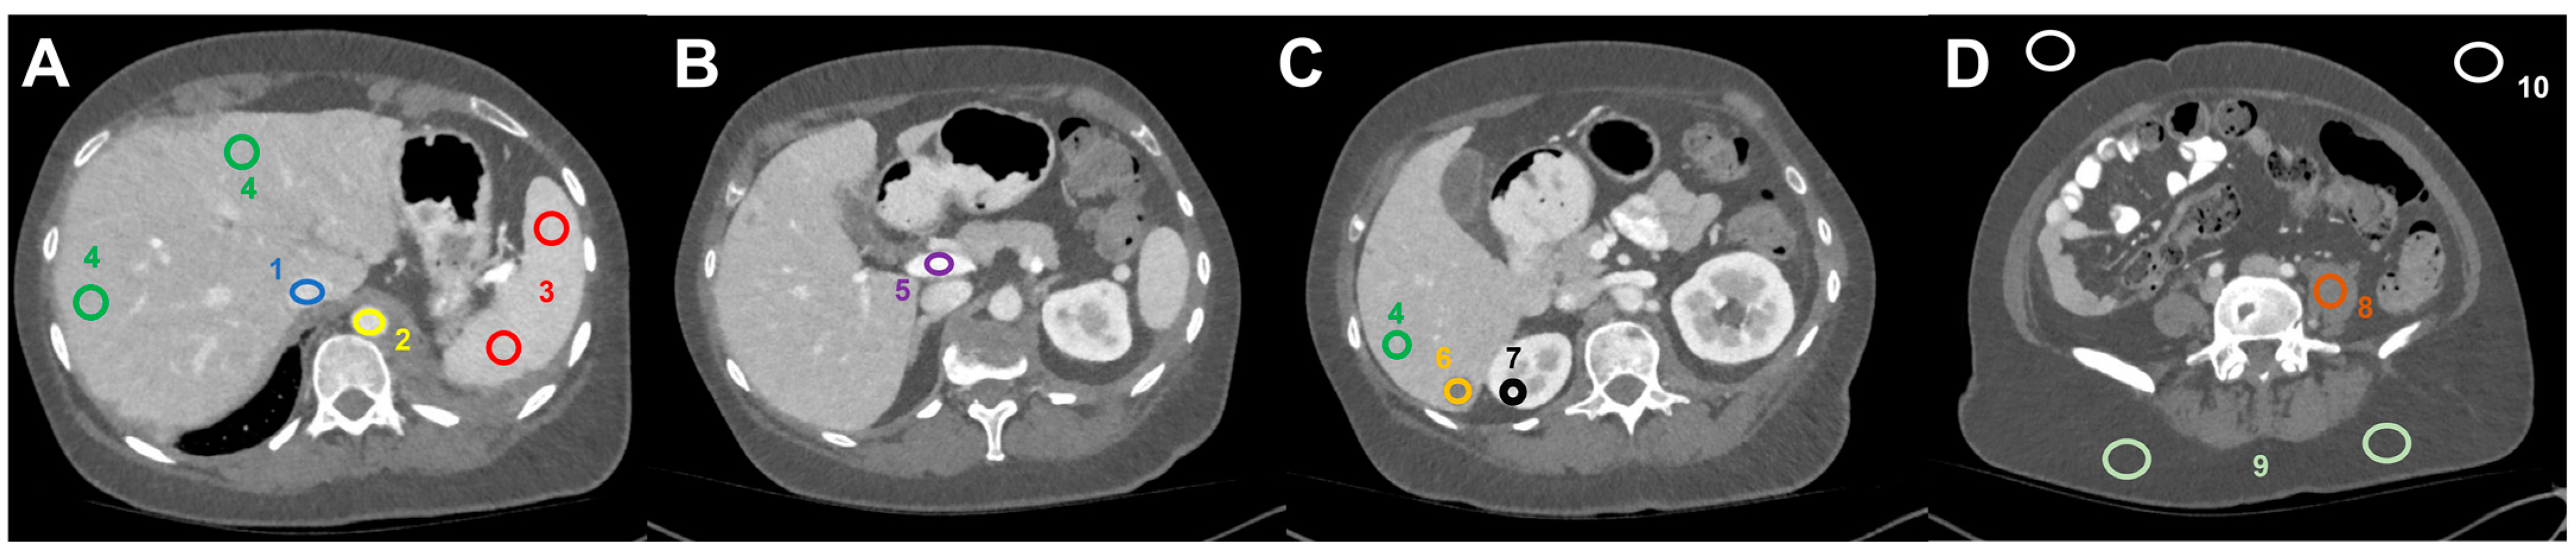

Image analysis was performed using the open-source software Fiji [21], an image processing package based on Image J. For each patient, 18 Regions of Interest (ROI)–with a size individually selected as large as possible while still encompassing homogenous tissue areas–were manually positioned in the following distinct anatomic regions on the 70 keV dataset and automatically copied to all other VMI-datasets (Figure 1): liver metastasis (3 ROIs per keV level); normal liver parenchyma (3 ROIs per keV level); inferior vena cava; aorta; portal vein; spleen (2 ROIs); renal cortex (right side); psoas muscle (left side); subcutaneous fat (right and left side); air (3 ROIs). ROIs were positioned in lesions with the highest visual conspicuity in patients with more than three metastases. Positioning of ROIs in EID-CT series was performed in analogy.

Figure 1.

Image analysis and ROI-based measurement of mean HU values (and standard deviation) in dedicated regions: (A) (1) inferior vena cava, (2) abdominal aorta, (3) spleen, (4) liver parenchyma, (B) (5) portal vein, (C) (6) liver metastasis, (7) right renal cortex, (D) (8) left psoas muscle, (9) subcutaneous tissue (2×), and (10) air (2×).